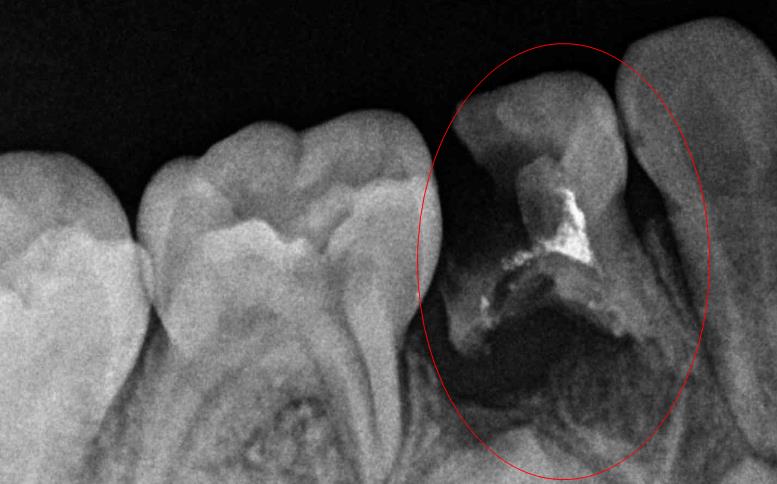

牙神經痛通常都是由於(yu) 牙齒壞掉感染到牙髓組織了,引起牙髓炎,如果不及時治療,會(hui) 慢慢發展為(wei) 根尖周炎,疼痛更為(wei) 劇烈。牙髓炎主要是冷熱的刺激疼痛,而且晚上疼痛嚴(yan) 重,好的辦法是第二天到醫院檢查,及時確診後開髓引流,釋放髓腔內(nei) 的壓力,一般可以馬上緩解疼痛。